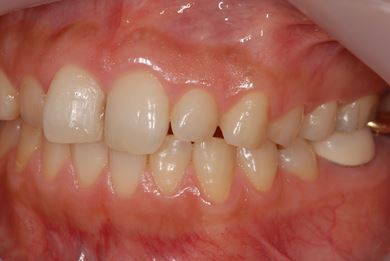

インプラントの症例写真 IMPLANT

インプラント治療+セラミック治療+歯肉歯槽骨整形

| 性別/年齢 | 女性 / 38歳 | ||||||||||||||||||||||||||||||||

| 主訴 | 右下奥の欠損のため、インプラントを希望。また、左に物が挟まりやすいための治療も希望。 | ||||||||||||||||||||||||||||||||

| 治療内容 | インプラント1本、ジルコニアフレームオールセラミッククラウン2本(ジルコニアセラミック用土台1本)、歯肉歯槽骨整形 | ||||||||||||||||||||||||||||||||